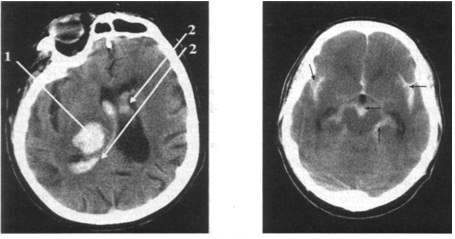

КТ головного мозга: визуализируется инсульт-гематома с прорывом крови в желудочковую систему; дислокация срединных структур влево, компрессия правого бокового желудочка: 1 - гиперденсивный очаг в правой височно-подкорковой области, обусловленный кровоизлиянием; 2 - кровь в боковых же­лудочках мозга КТ головного мозга: спонтанное субарахноидальное кровоизлияние; визуализируется кровь (гиперденсивная) в цистернах мозга, щелях и подпаутинных пространствах (показано стрелками)

КТ дает возможность надежно диагностировать субарахноидальное кровоизлияние (см. рис. 102). Стандартная ангиография, транскраниаль­ная допплерография позволяют выявить локализацию разрыва аневризмы только в области сегмента большого артериального круга мозга. Обычная КТ-ангиография, выполненная в течение первых суток после развития суб­арахноидального кровоизлияния, дает возможность определить лишь лока­лизацию разрыва аневризмы средней мозговой и соединительной артерий. Высокоинформативными методами диагностики являются МР-ангиография и дигитальная субтракционная ангиография. Они позволяют визуализиро­вать небольшие по размеру аневризмы, а также развитие ангиоспазма.